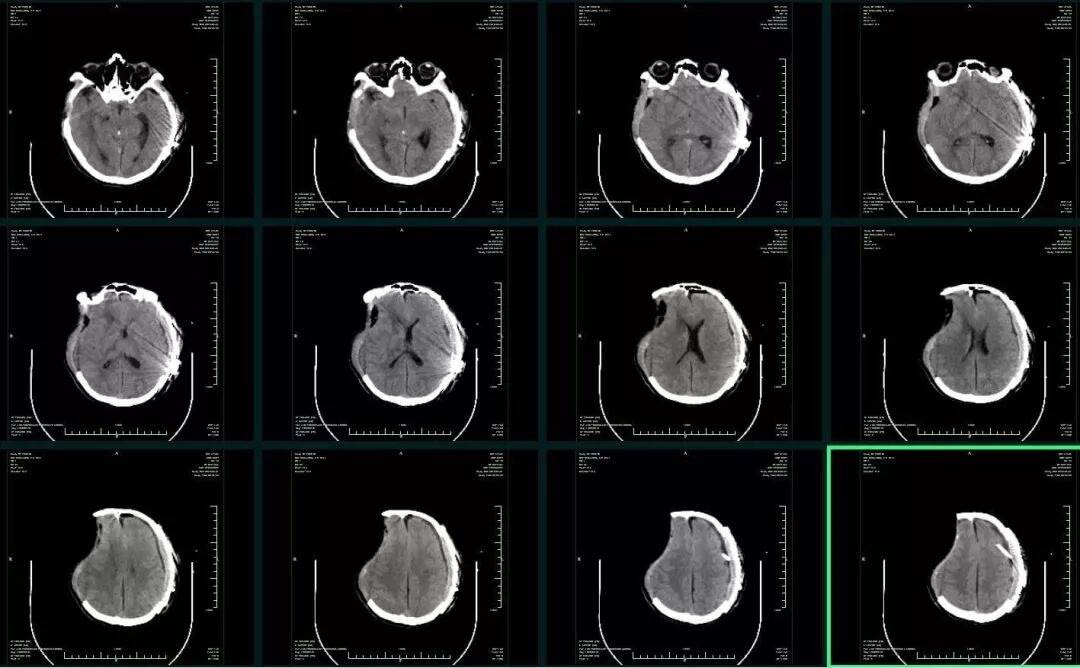

入院时患者深昏迷,GCS6分,左侧瞳孔0.5cm,右侧瞳孔0.3cm,对光反射均消失。急诊头颅CT提示:“左侧额颞顶部急性硬膜外血肿,脑疝(图1)”,急诊行左侧颅内血肿清除+去骨瓣减压术,术后即刻头颅CT复查提示:“右侧额颞叶急性硬膜下血肿”(图2),再次开颅行右侧颅内血肿清除+去骨瓣减压术。术后转ICU科呼吸支持治疗。术后再次复查CT,见血肿已清除,无硬膜下积液,中线基本居中(图3)。术后5天患者病情好转,GCS8分,双侧瞳孔0.3cm,对光反射迟钝,转回神经外科监护病房。

图2. 左侧急性硬膜外血肿清除+去骨瓣减压术后,出现右侧急性硬膜下血肿。